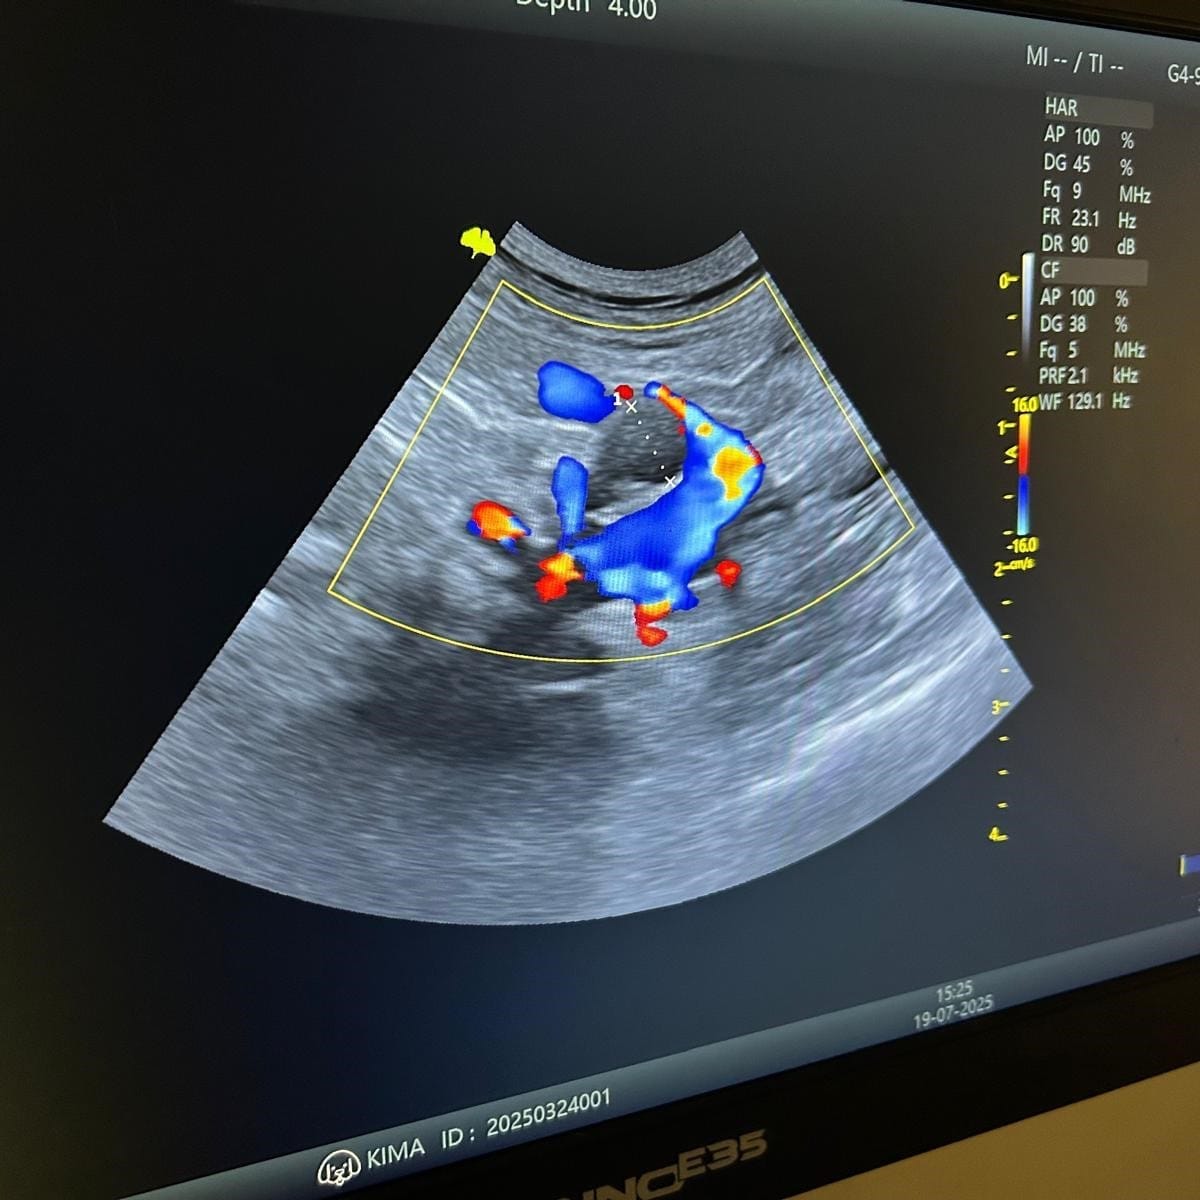

Aprender ecografia abdominal com pacientes

Workshop Prático de Ecografia Abdominal

Ganha confiança na tua técnica e diagnóstico ecográfico através de um curso prático e pessoal.

Neste workshop vamos aprender ecografia de todos os órgãos abdominais, incluindo adrenais, pâncreas e linfonodos, e as diferenças anatómicas entre cão e gato.